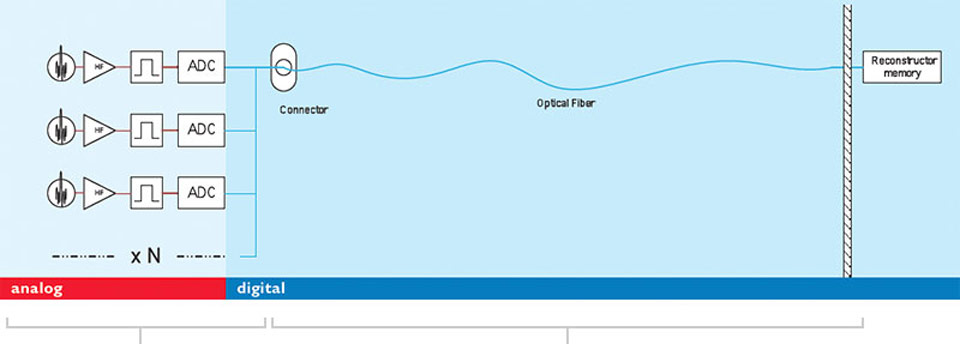

La arquitectura de dStream utiliza un método de muestreo DirectDigital RF para la digitalización: la señal de imagenología de resonancia magnética (IRM) se muestrea directamente, sin conversión a CD. Esta técnica evita todas las etapas analógicas intermedias para la conversión descendente de la señal entre el elemento de la bobina y el convertidor de la configuración analógica a digital (ADC).

La digitalización tiene lugar en la propia bobina. La electrónica de la ADC ha sido miniaturizada y colocada dentro de la bobina.

Un cable de fibra óptica para cualquier número de canales de radiofrecuencia (RF) reemplaza múltiples cables coaxiales y mantiene la calidad de la imagen. El número de canales de RF ya no es una especificación del sistema.

Arquitectura de dStream

Una explicación visual de la arquitectura de dStream.